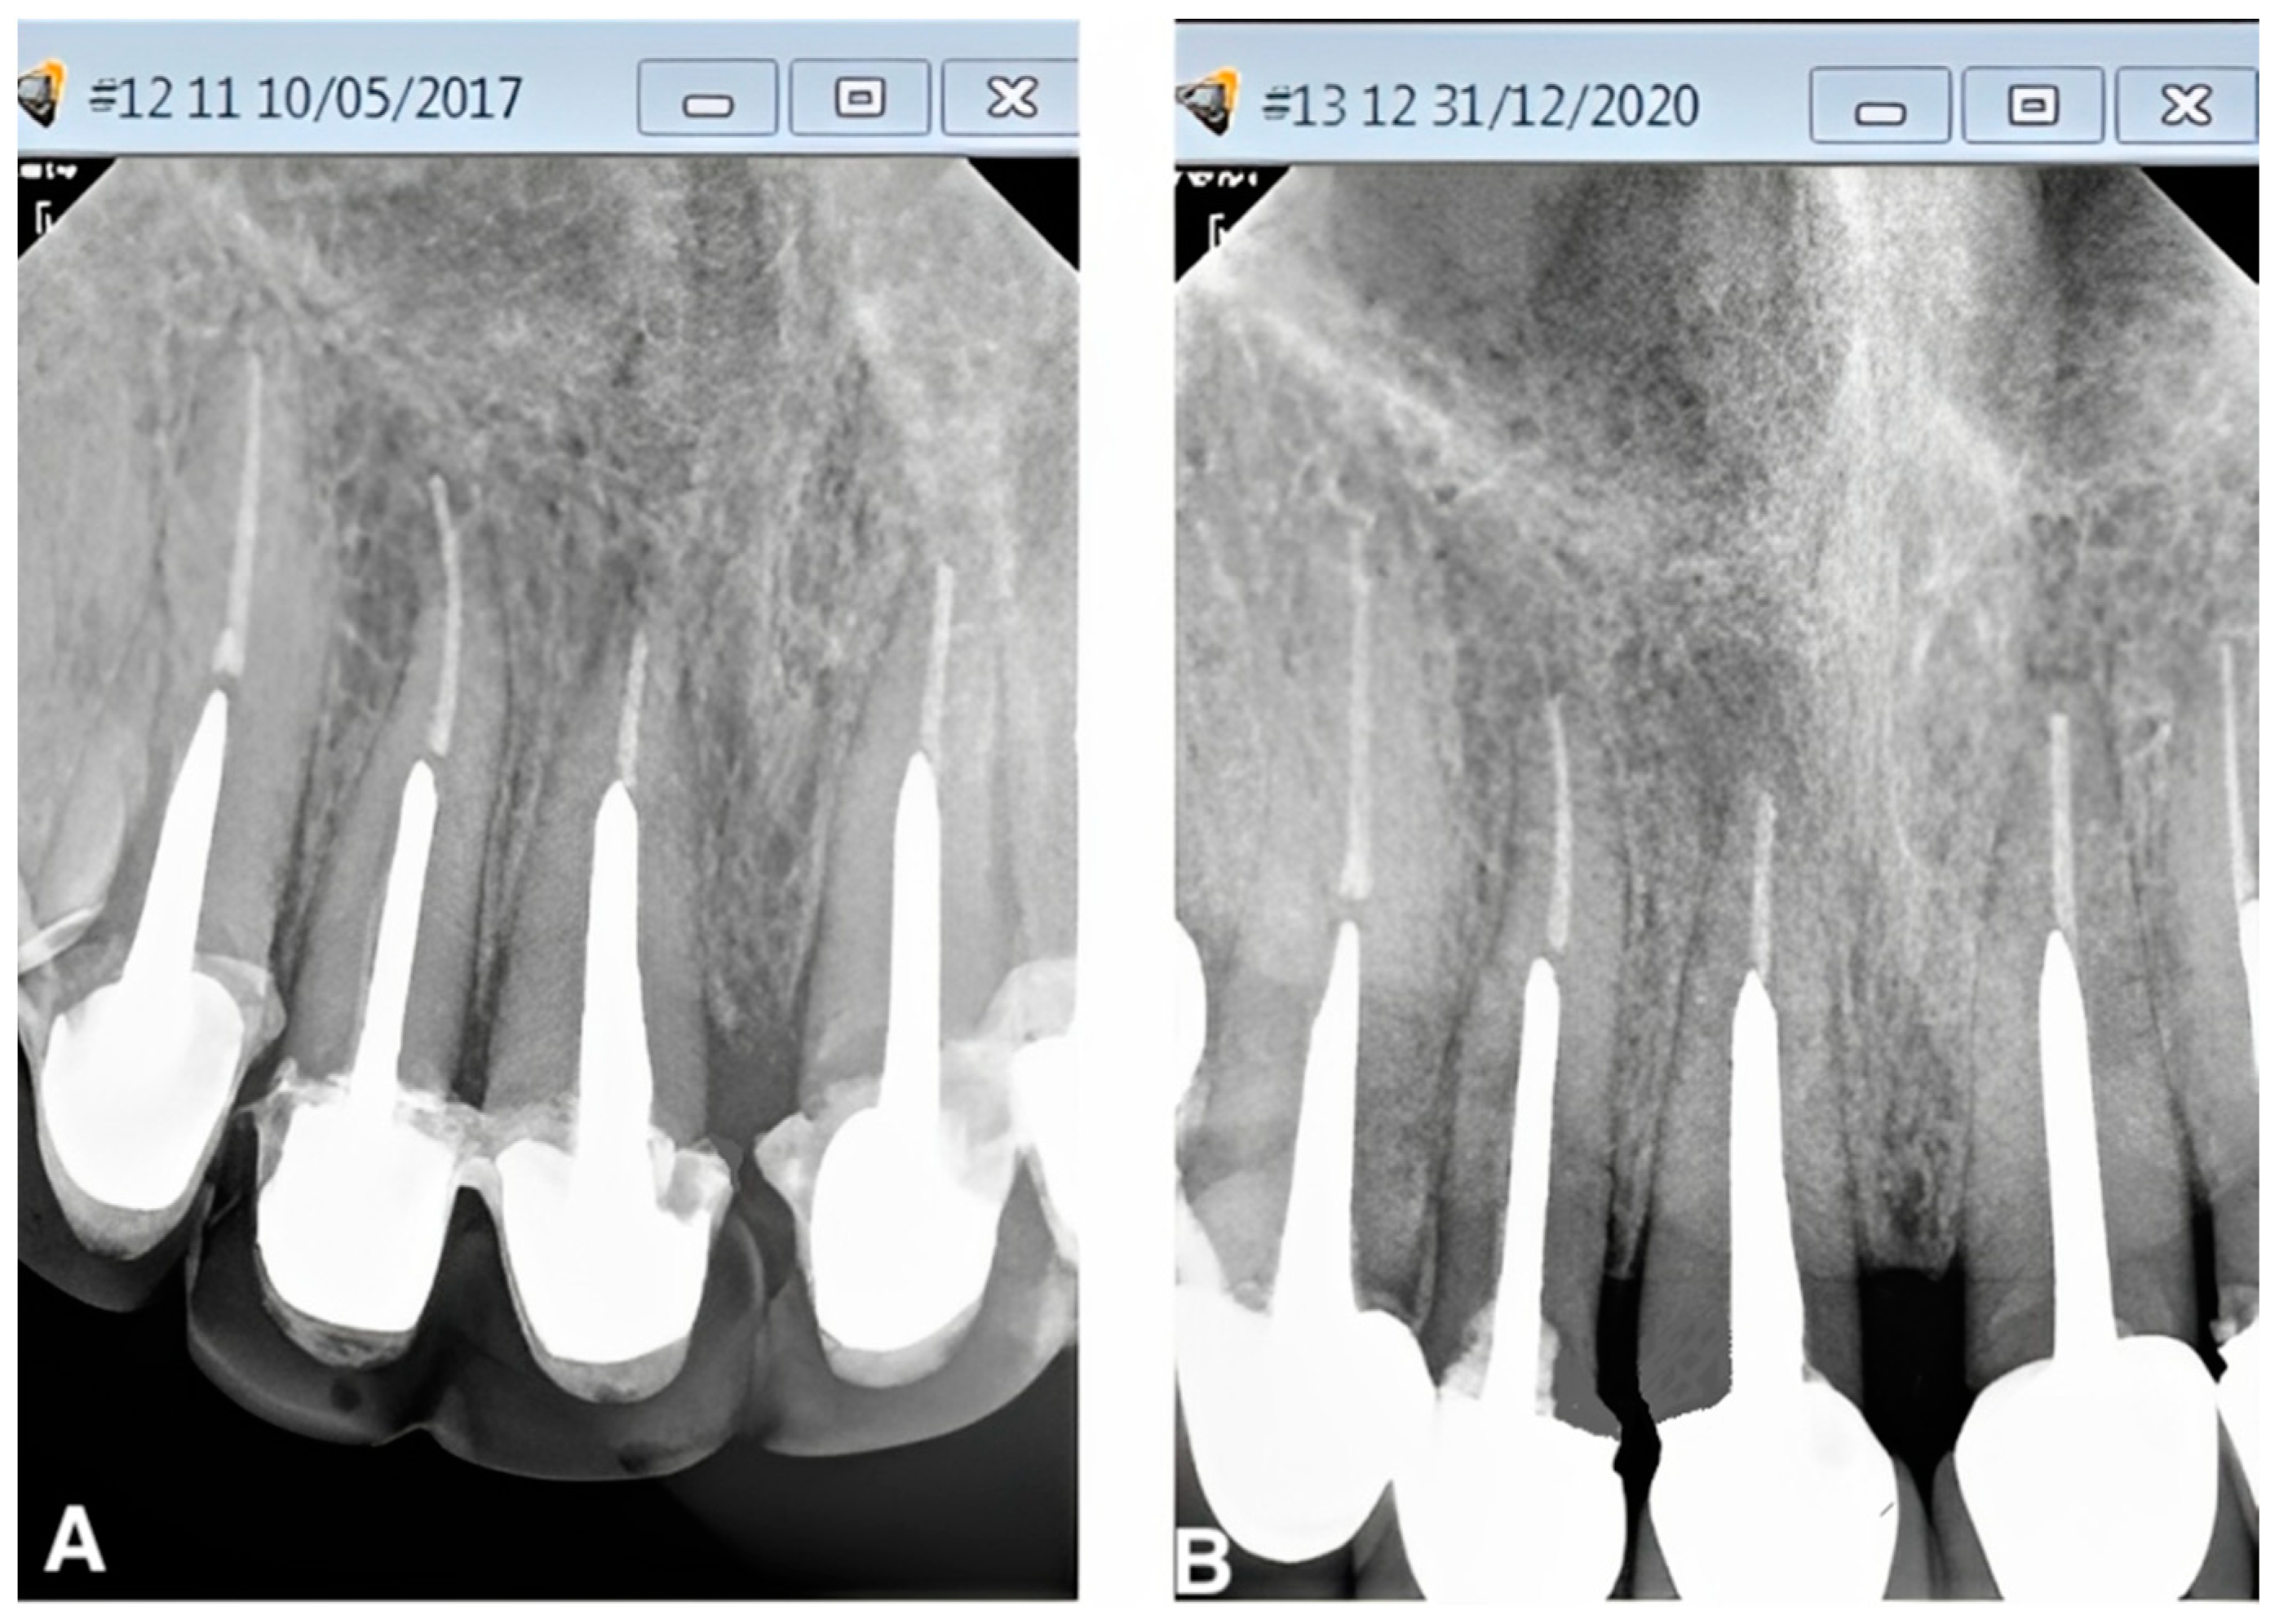

From www.researchgate.net

(A and B) Clinical aspect and radiographic tracking with a guttapercha Gutta Percha Side Effects Learn about the benefits and drawbacks of root canal treatment, a procedure to preserve a decayed tooth. Find out why you may need a root canal, what happens during and after the procedure,. Learn about root canal treatment for infections in tooth pulp, the innermost layer of your teeth. Find out the causes, process,. Find out the signs, causes,. Gutta. Gutta Percha Side Effects.